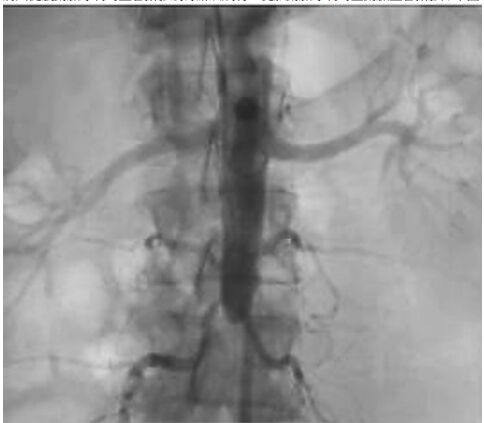

14.病人從股動脈穿刺的血管攝影沒有辦法成功,從肱動脈穿刺的主動脈血管攝影如下圖,診斷應為下列何者?

(A)遠端主動脈阻塞 (B)腎臟的動靜脈畸型 (C)腹腔動脈阻塞 (D)上腸繫膜動脈阻塞